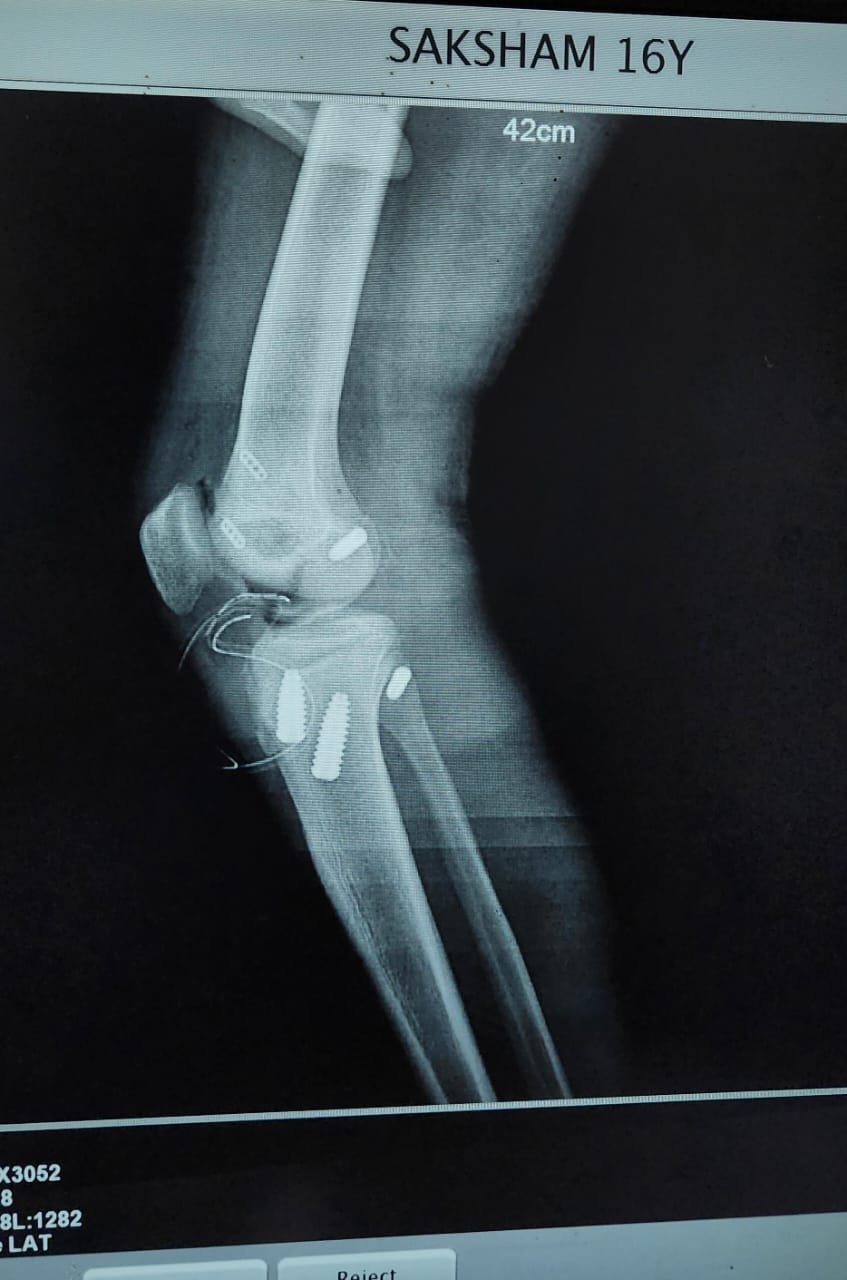

- ACL Reconstruction

- PCL Reconstruction

- Arthroscopy-Knee

- Fracture Treatment